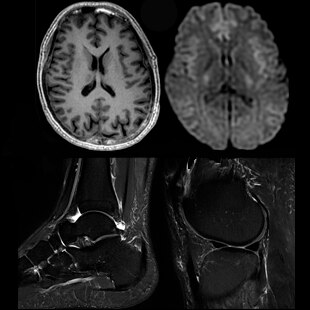

Soothing Silence

With SilentSuite, which is both revolutionary and proprietary, the SIGNA Pioneer reduces dB levels from an ear-splitting, motorcycle-level 91dB to within 3dB of scan room ambient noise. Along with this dramatic advance comes the first-ever complete Silent Neuro Exam that includes Diffusion Weighted Imaging (DWI).

In addition, we have expanded our Silent imaging capability beyond neuro imaging to musculoskeletal and spine imaging.